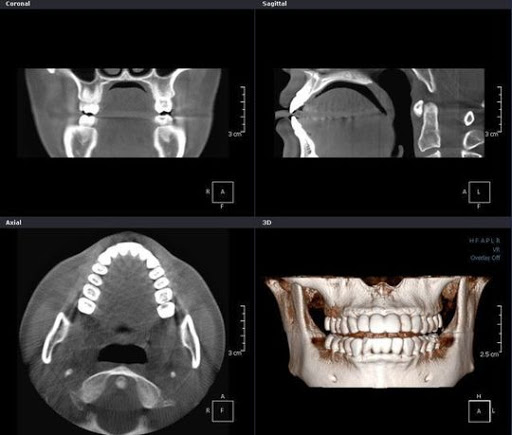

これらを回避するにはCT等を使った診査診断や解剖学的形態の把握が重要になります。

当院ではインプラント治療を行う前には必ずCT撮影、模型診断を行い、安全にインプラント治療が行える状態かを診断してから手術を行います。

手術時には徹底した感染対策を取った上で、わずかなズレも起こらないようガイデッドサージェリーを行なっております。